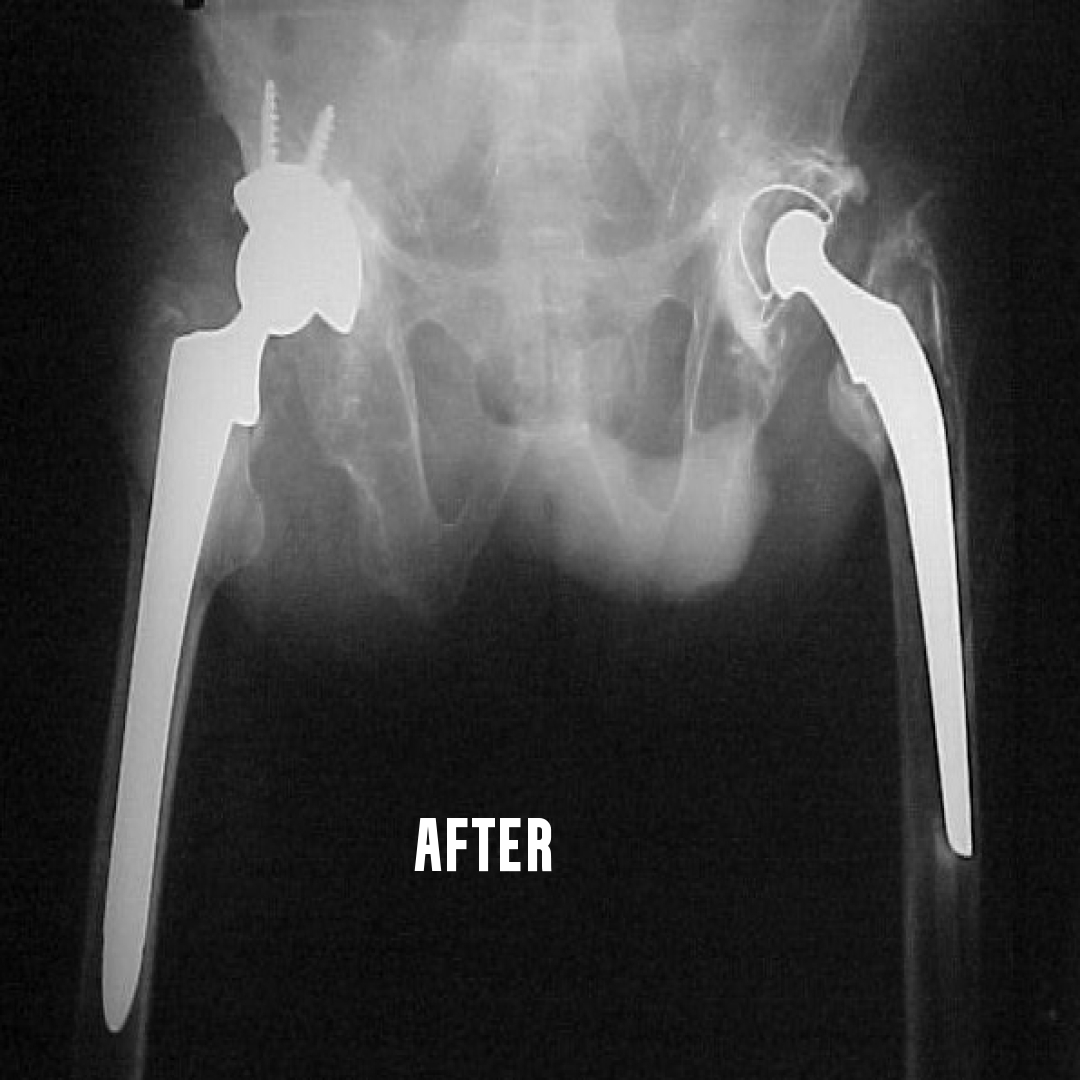

This is a surgery where both the ball and socket of the hip joint are replaced with artificial materials.

The normal hip joint consists of a cup called the acetabulum into which articulates a head of the thigh bone called the femur.

This joint may become damaged due to a variety of conditions. The common

causes are rheumatoid arthritis, ankylosing spondylitis, childhood diseases

like perches, injury to the hip joint etc. There is loss of articular cartilage, a

smooth lining of the ends of the bone in a joint. The result is that raw bones rub against each other causing pain. This condition where the articular

cartilage is damaged, is collectively called arthritis.

Damage to hip joint can occur at any age. Total hip replacement can be done

after the age of 20 years...Learn More

Done for failed joint replacement due to infection, aseptic loosening, fracture around the implant etc. The surgery is more complicated, and the results depend on intense post operative

physiotherapy. Surgery is undertaken after thorough examination, adequate investigations regarding the cause of the failure and after a detailed interview with the patient and his relatives.

Infected replacement revisions are done as two stage procedure. Fix up an appointment if you need further information